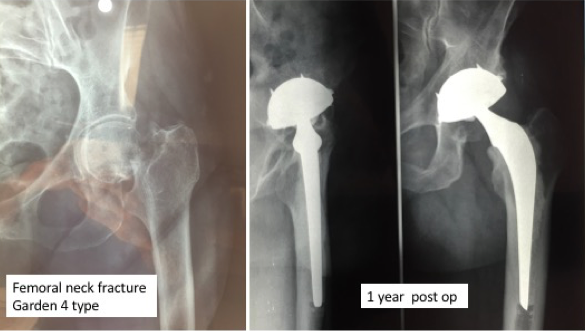

Clinical scores (PMA, HSS) and radiological (Figure 2) analysis based on a standard regular follow-up of 3 months, 1 year, 2 years and then every 2 years. Any intra-operative or postoperative complications are recorded.

Figure 2.Femoral neck fracture Garden 4 treated by THA. Cementless DMC with cemented Charnley femoral component.